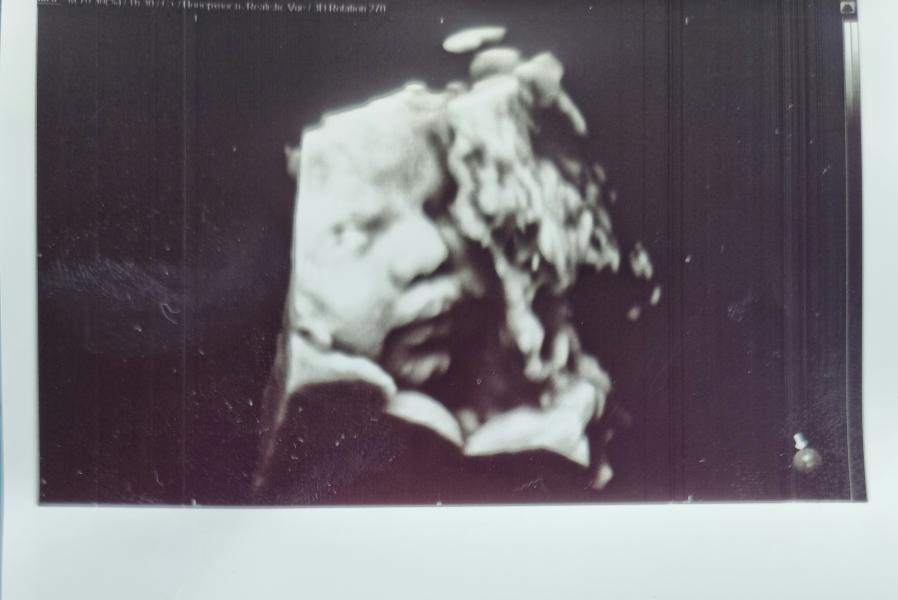

Неделя до 3 марта! Как там губастик? Мама ещё не собрала вещи в роддом, что делать?

Пошёл обратный отчёт, осталась всего неделя.Ждем 3.03,надеюсь губастик не захочет вылезти раньше,ведь мама до сих пор не сложила вещи в роддом😅